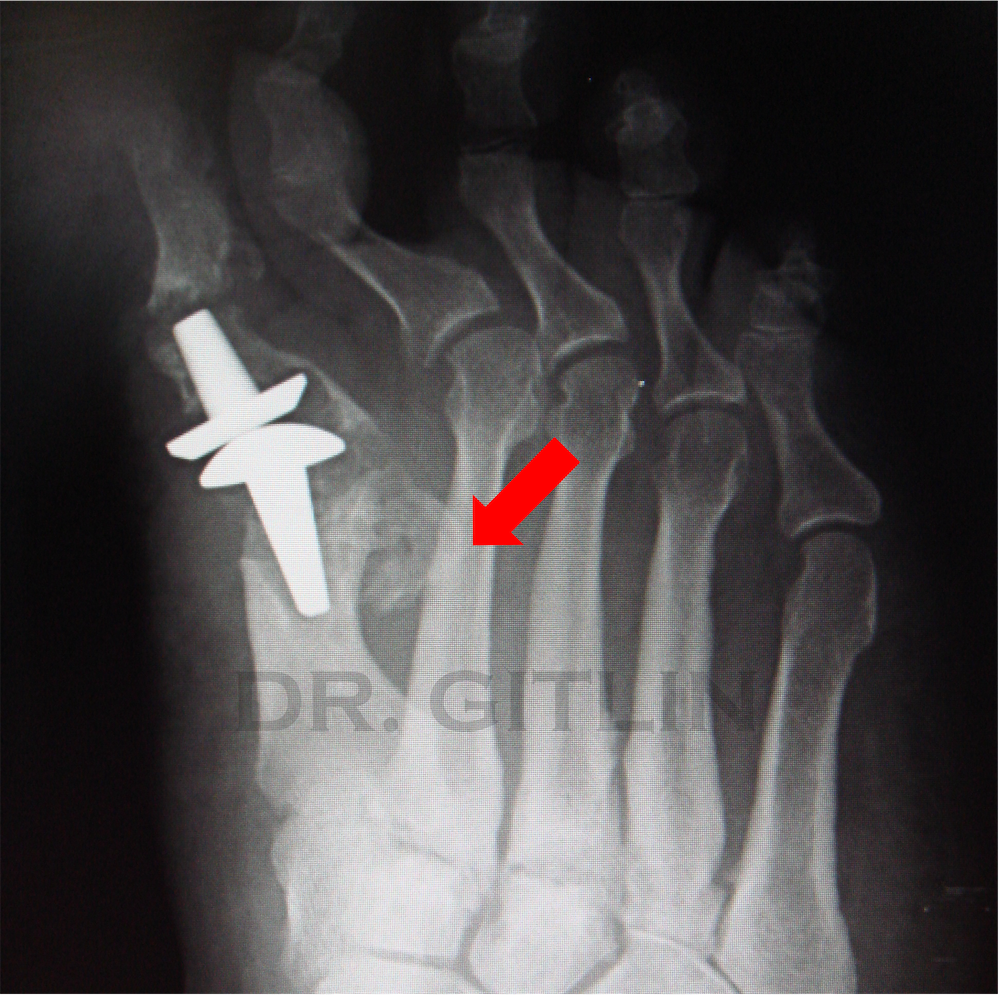

In the xray above you can see a total implant of the big toe joint that has loosened and broken through multiple other bones. The two main bones of the joint are completely destroyed and infected. In the next phot you can see the implant we have removed. These types of two part (component) implants are not popular anymore because of exactly this situation. When they need to be removed a large section of bone is removed with them. Todays implants are much smaller but of course not without their own issues.

We removed the implant and all the bad bone around it. and then we cut out the bone right next to it. Also called a metatarsal that attaches to the second toe. And we moved that bone into the space of the first metatarsal bone. We decided the first metatarsal was more important for stability of the foot so we sacrificed the second metatarsal. The RED arrow in the pictures points to the second metatarsal so you can follow where it came from and where it ended up. We used an external fixator that is also pictured here to hold the bones together and allow the patient to walk immedialty after surgery.